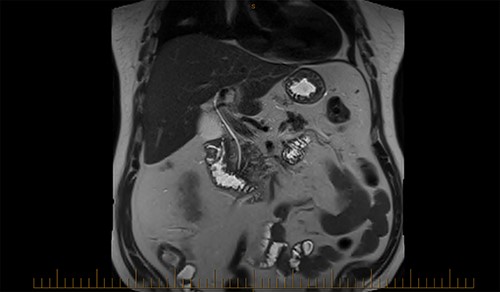

A magnetic cholangiopancreatography (MRCP) was performed to exclude a cholecystoduodenal fistula. A filling defect within the duodenum was identified on the scan; however, there was no evidence of a fistula (Fig. 6).

On Day 7, a repeat upper gastrointestinal endoscopy was performed. The FB remained in the first part of the duodenum which it had begun to erode through posteriorly (Fig. 7). The endoscopy was fitted with an overtube and with the help of a snare the embedded FB was successfully retrieved.